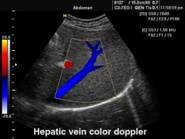

В Центре современных медицинских технологий «АКВА МЕД МАРИН» прием ведет врач УЗД высшей категории со стажем более 20лет - Пахалюк Александр Александрович. УЗИ-диагностика проводится на новейшем ультразвуковом диагностическом сканере Экспертного класса SonoScape S40Exp, в том числе и УЗИ детям с применением специальных детских датчиков. Цветной допплер помогает точной диагностике патологии сосудов и сердца у взрослых и детей.

Компания SonoScape уделила особое внимание допплеровским режимам и является экспертом в своем классе, что позволяет с легкостью, но в то же время с уникальной точностью проводить исследования с постановкой наиболее точного диагноза.

Ультразвуковые исследования, доплеровское сканирование сосудов в Центре современных медицинских технологий «АКВА МЕД МАРИН» выполняется при помощи первого и единственного аппарата в Керчи SonoScape S40Exp (экспертного класса, который оснащен множеством новейших функций, многократно улучшающих качество и информативность УЗИ-исследования).